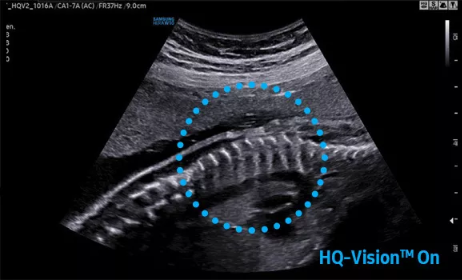

2D成像方面,Hera i10集成了包括ShadowHDR?、HQ-Vision?、ClearVision等多項具有三星“血統(tǒng)”的技術(shù),加強了圖像的陰影抑制、減少偽影、緩和模糊區(qū)。